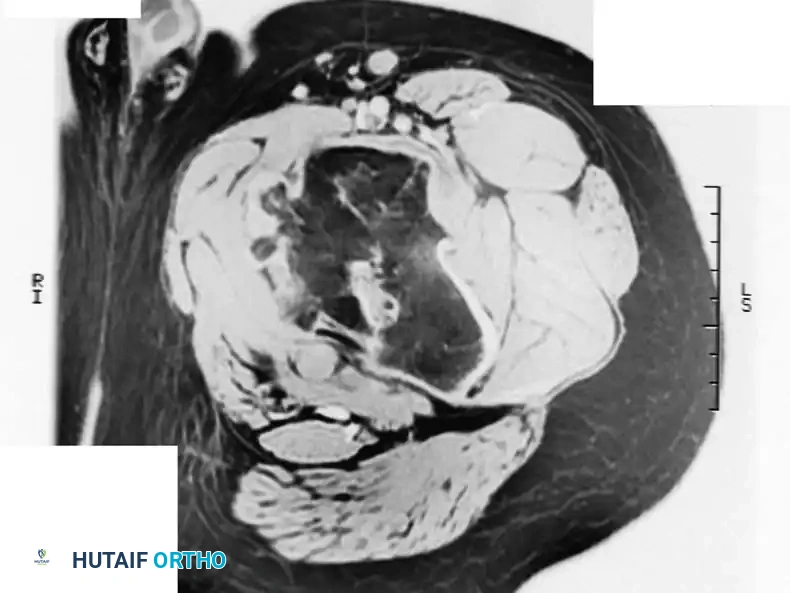

Magnetic Resonance Imaging (MRI): MRI is invaluable for assessing the marrow extent and identifying any associated soft-tissue mass. An associated soft-tissue mass is never present with an uncomplicated enchondroma; its presence is pathognomonic for a malignant process (chondrosarcoma). On MRI, cartilage lesions typically demonstrate low-to-intermediate signal intensity on T1-weighted images and characteristically high signal intensity on T2-weighted images due to the high water content of hyaline cartilage.

MRI (T1-weighted) demonstrating a dark, well-circumscribed medullary lesion.

MRI (T2-weighted) of the same lesion.